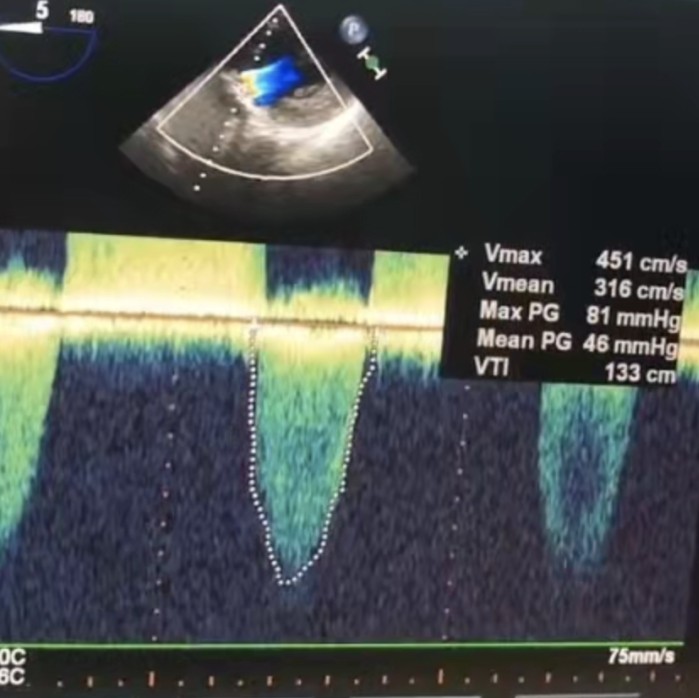

术后效果:

瓣膜释放后形态位置良好,造影几乎无瓣周漏

术后超声微量瓣周漏

跨瓣压差3mmHg

患者:女性,71岁,以间断胸闷气短4年为主诉入院,术前诊断:1.冠心病2.高血压病2级3.主动脉瓣重度狭窄二尖瓣重度关闭不全4.心律失常,三度房室传导阻滞。术前峰值跨瓣压差 120mmHg,瓣上速度 4.5m/s,瓣口面积0.8cm²。